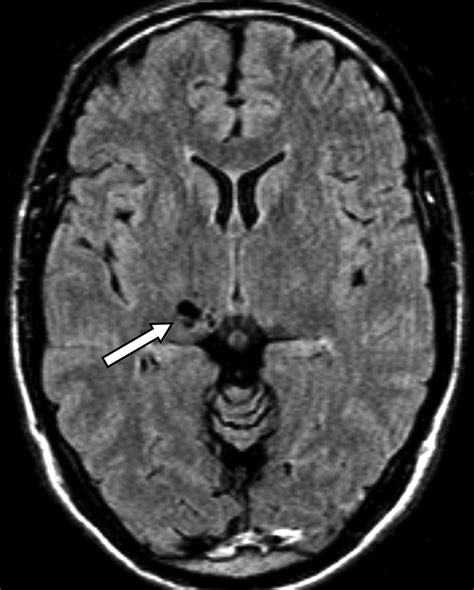

This creates a small, fluid-filled gap between the vessel wall and the brain parenchyma (the functional tissue of the brain). This gap is the perivascular space. The fluid inside these spaces is cerebrospinal fluid (CSF), which is the same clear fluid that cushions the brain and spinal cord. Because they are filled with CSF, they appear dark on T1-weighted MRI images and bright on T2-weighted images, mirroring the signal intensity of the CSF in the rest of the brain's ventricles.

Most individuals have perivascular spaces that are too small to be detected by standard imaging equipment. However, as people age, or under certain physiological conditions, these spaces can dilate or become more prominent. When they reach a size that is visible on an MRI, they are often referred to as prominent perivascular spaces.

Radiologists look for these spaces frequently. They are most commonly found in the basal ganglia, the deep white matter, and the area surrounding the brainstem. Their visibility is not necessarily an indication of pathology; rather, it is often simply a characteristic of the brain's unique anatomy. Several factors can influence their visibility: